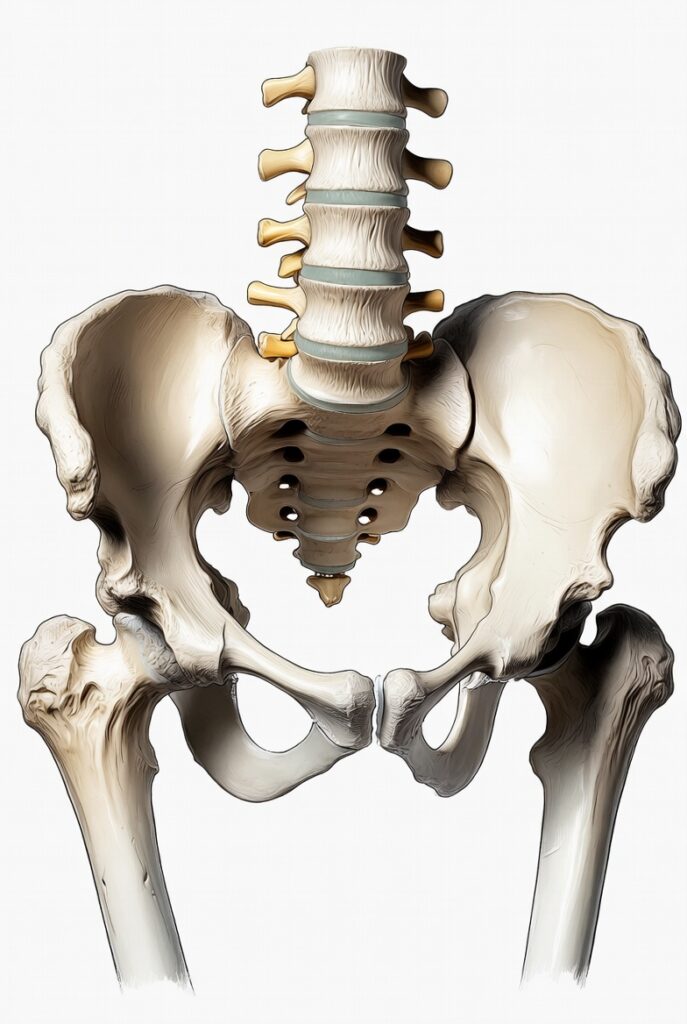

Prenons l’exemple du bassin : s’il est en perte de mobilité, cela peut perturber la posture générale et provoquer des tensions sur les structures qui y sont suspendues, comme le côlon ou le rectum. Il en va de même pour la colonne vertébrale, notamment au niveau thoracique et lombaire, qui est en relation étroite avec les nerfs innervant les organes digestifs. Une hypomobilité vertébrale peut alors avoir des conséquences sur la motricité intestinale.

L’ostéopathe va évaluer et traiter à la fois le cadre osseux (colonne vertébrale, bassin, côtes) et les organes viscéraux eux-mêmes. Grâce à des techniques manuelles précises, il va restaurer la mobilité des différentes structures et leur harmonie.

- Des mobilisations du bassin peuvent soulager une constipation chronique en redonnant de l’espace et du tonus aux organes pelviens.